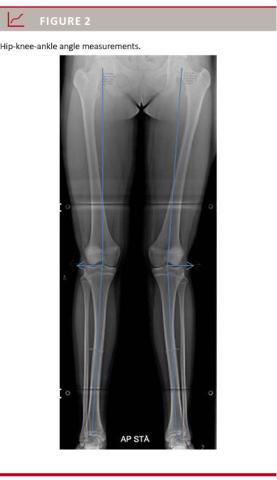

The HKA angle is the angle between the mechanical axis of the femur and the tibia [4, 6]. It is obtained by connecting the centre of the femoral head to the midpoint of the tibial eminential spine in a line tangential to the femoral condyles, and another line from here to the centre of the trochlea tali (Figure 2)

. The HKA angle can also be expressed as x degrees of deviation from a neutrally aligned lower extremity (180°) [9]. We measured the length of the tibia and the femur along the anatomical axis. The radiographs were primarily obtained in a standardised fashion, and all HKA angles, tibia and femur lengths, were measured using Impax 6.3.1 (AGFA HealthCare, Denmark). All measurements were made by the same radiologist (MBH). For data analysis, the right and the left HKA angles were added to allow data to be correlated with the measured IM distances.